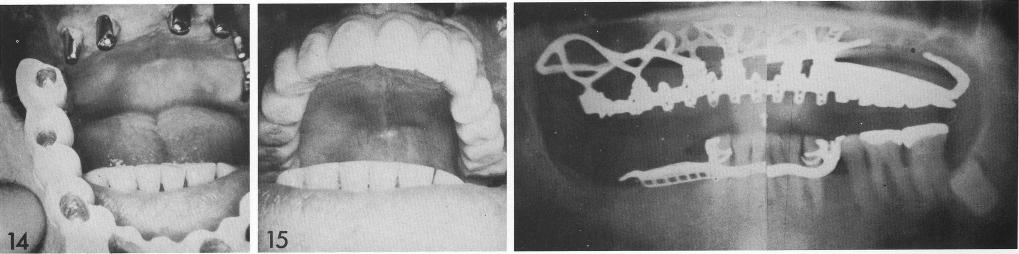

Atypically a double-posted bladevent serves as anchorage for two types of subperiosteal implants. The patient was totally edentulous (I), and two double-posted bladevents were inserted on each side of the midline (2-4). A pterygoid extension implant covering three abutment posts and spanning approximately three-fourths of the arch was fabricated (5), together with a unilateral subperiosteal implant with an anterior coping (6), the anterior anchorage of which was the distal post of the right bladevent whose proximal post was already included in the pterygoid extension implant. In this manner both sides of the arch were splinted the same as a full-arch splint after the implant copings were cemented to the bladevent posts. The subperiosteal type implants were inserted in the same session over the bladevents (7 through 11), and the tissues closed (12). The patient was dismissed until the tissues healed (13). The final full-arch restoration (14) was cemented over the abutment posts (15).

1 Full maxillary arch restoration cemented over abutment implant posts